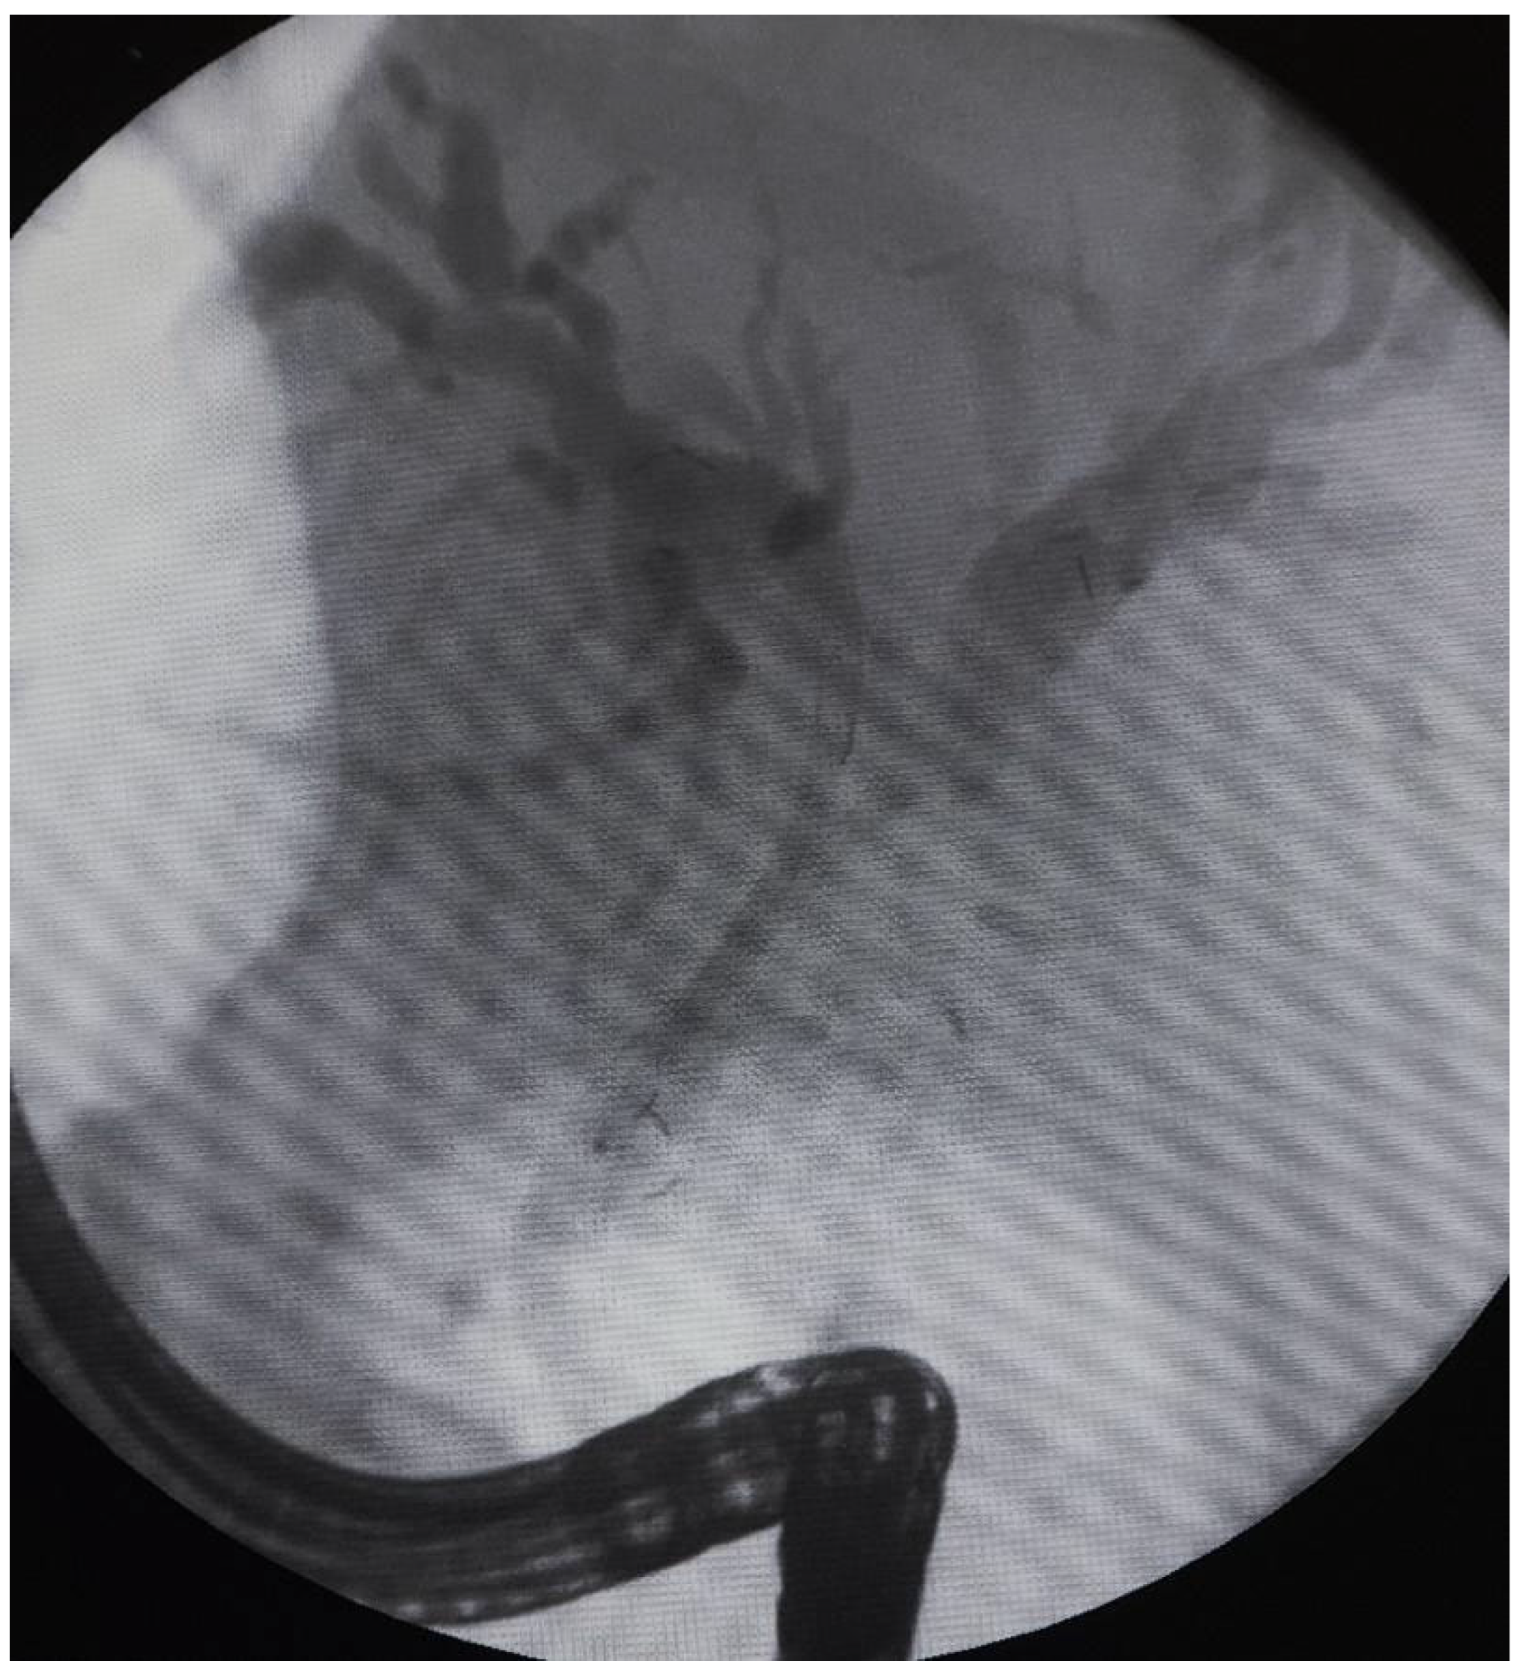

The data from 24 consecutive patients with bile duct stenosis due to non-resectable HC who underwent RFA with bile duct stenting in our department between 05.2020–05.2024 were collected retrospectively from electronic medical records and analyzed. Patients with malignant biliary stenosis had diagnoses of unresectable HC, PDAC in the head of the pancreas, and adenocarcinoma of the gallbladder. Inclusion criteria for RFA treatment included patients with recurrent mechanical jaundice due to cancer progression despite a previous biliary prosthesis. High-power radiofrequency ablation of the narrowed biliary segments, followed by reimplantation of SEMS, Amsterdam stents, or double pigtail (DPT) into their lumen, was performed in 24 patients (19 women and 5 men). The procedure was performed under intravenous sedation using a PENTAX-ED-34 and 10t2 duodenoscope. RFA was carried out with a power setting of 7–14 watts and a temperature of 75–80°C. The following stents were used for the procedure: uncovered SEMS (10x80 mm, 10x60 mm, 10x100 mm), Large Cell D-type stents (LCD) (10x60 mm), fully-covered SEMS (8x80 mm), Amsterdam-type plastic stents (12cm 10 Fr, 9cm 10 Fr, 12 cm 8.5 Fr, 12 cm 7 Fr), and self-expandable BIL-0-10-60-RP stents. Figures 2, 3, and 4 present the RFA catheter and stents’ configurations (Figure 2, Figure 3, Figure 4).

Figure 2. The RFA catheter (StarMed ELRA) during the ablation procedure.